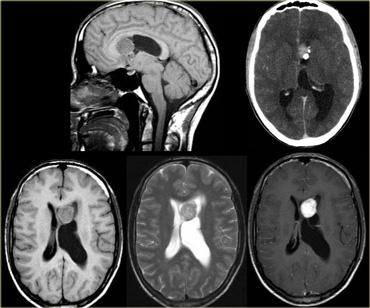

Ngấm thuốc dạng vòng

Ngấm thuốc dạng vòng được thấy trong di căn não và u thần kinh đệm độ cao.

Nó cũng được thấy trong các tổn thương không phải u như áp xe, một số mảng xơ cứng rải rác (MS) và đôi khi trong khối máu tụ cũ.

Bên trái là ba tổn thương ngấm thuốc dạng vòng khác nhau.